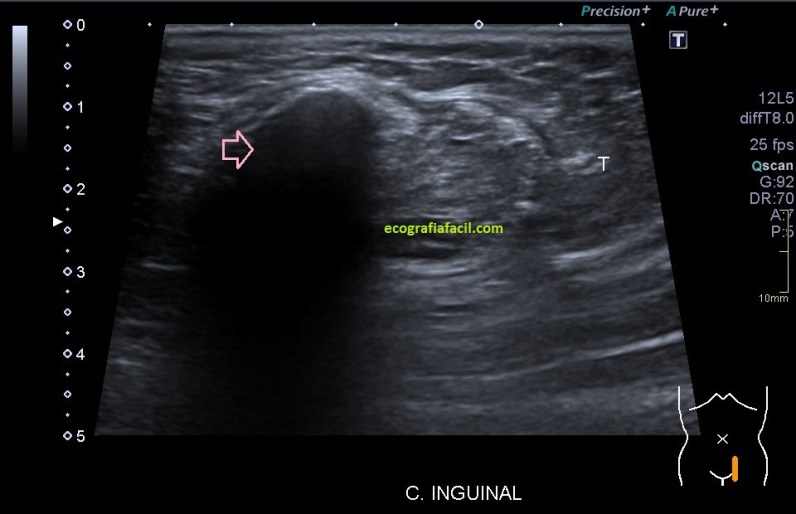

Toca ahora después de la localización y estudio, las medidas que arrojaban una lesión bastante grande.

Llamaba poderosamente la atención, fue la enorme calcificación con una potente sombra posterior que te indica la flecha rosa y que atesoraba esta lesión, refrendada a posteriori en el estudio de Ct como puedes ver en la imagen número 7.

En segundo término, la heterogenicidad global de la imagen, clave para el diagnóstico, la semiología tan llamativa de la ecoarquitectura.